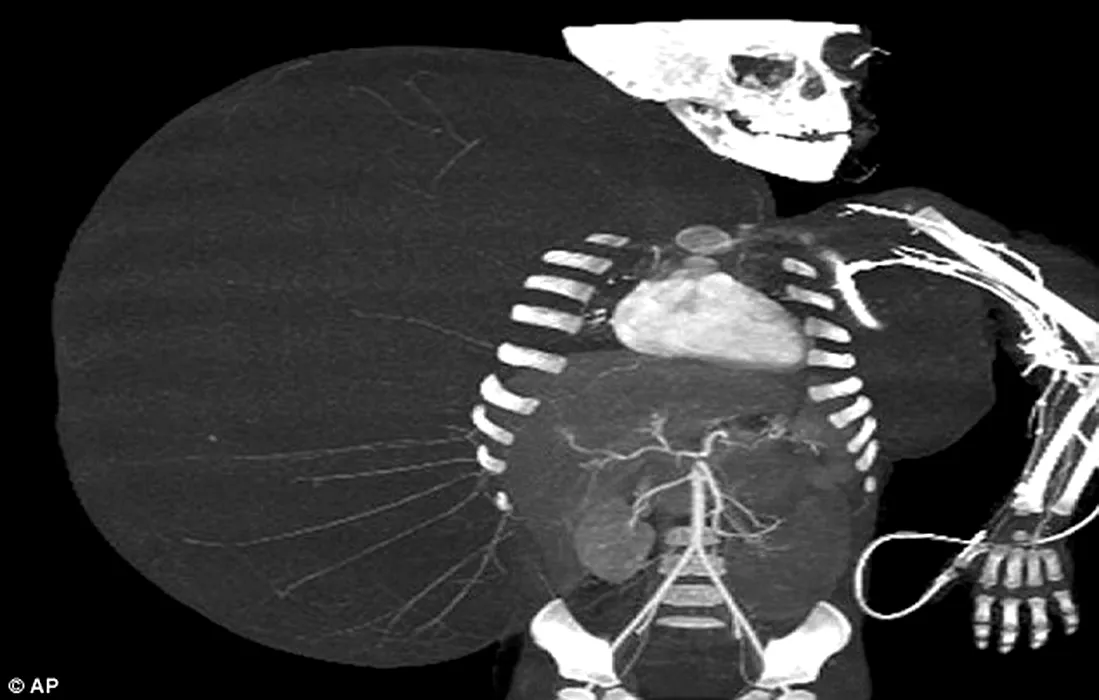

Premieră medicală în Mexic. Chirurgii au reușit extirparea unei tumori care cântărea mai mult decât pacientul